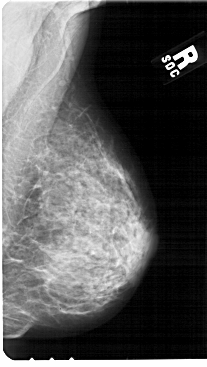

A_1851_1.RIGHT_CC

RIGHT_CC LINES 5491 PIXELS_PER_LINE 2956 BITS_PER_PIXEL 12 RESOLUTION 43.5 NON_OVERLAY